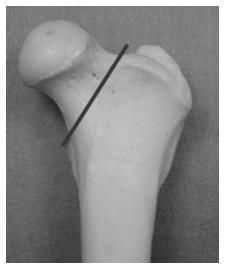

Une dissection des muscles de la hanche est réalisée jusqu’à exposer l’articulation de la hanche. Une section du col fémoral permet le retrait de la tête et du col fémoral puis les plans musculaires, sous-cutané et cutané sont refermés.